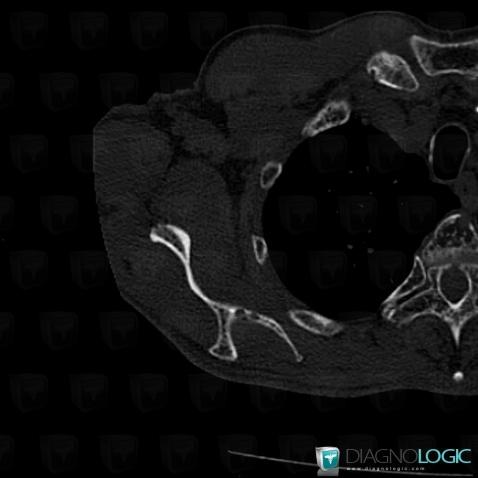

Multiple myeloma, Scapula, CT

Here is the specific information in the key image above:

- Diagnosis Multiple myeloma, Location(s) Scapula, with gamuts Mulltiple osteolysis, Ill-defined osteolysis